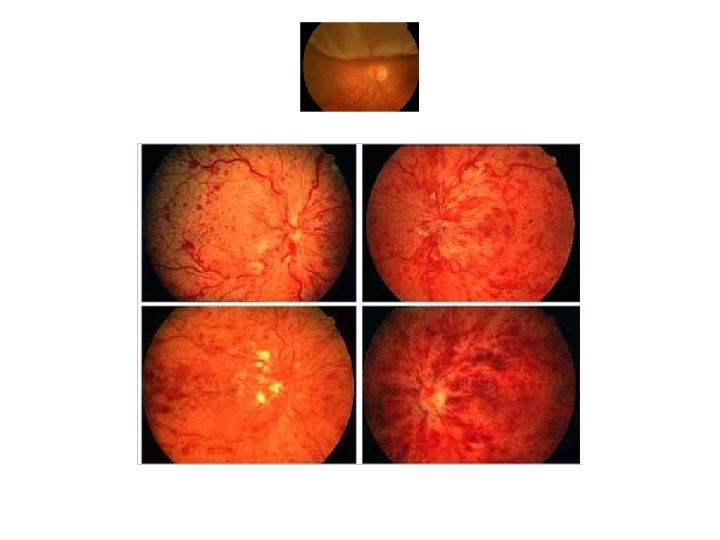

Observation of the fundus structures is very important for clinical diagnosis.

Evaluation of retina & optic nerve • Observation: Compare between the two eyes, and compare with the population. • Correlate between BCVA, clarity of visual pathway and fundascopic findings • Relative afferent pupillary defect • Function tests: visual field, VEP, ERG, EOG. .

Retina & Optic nerve : Angiography, visual field, OCT, GDX, ERG, EOG, VEP, ultrasonography,